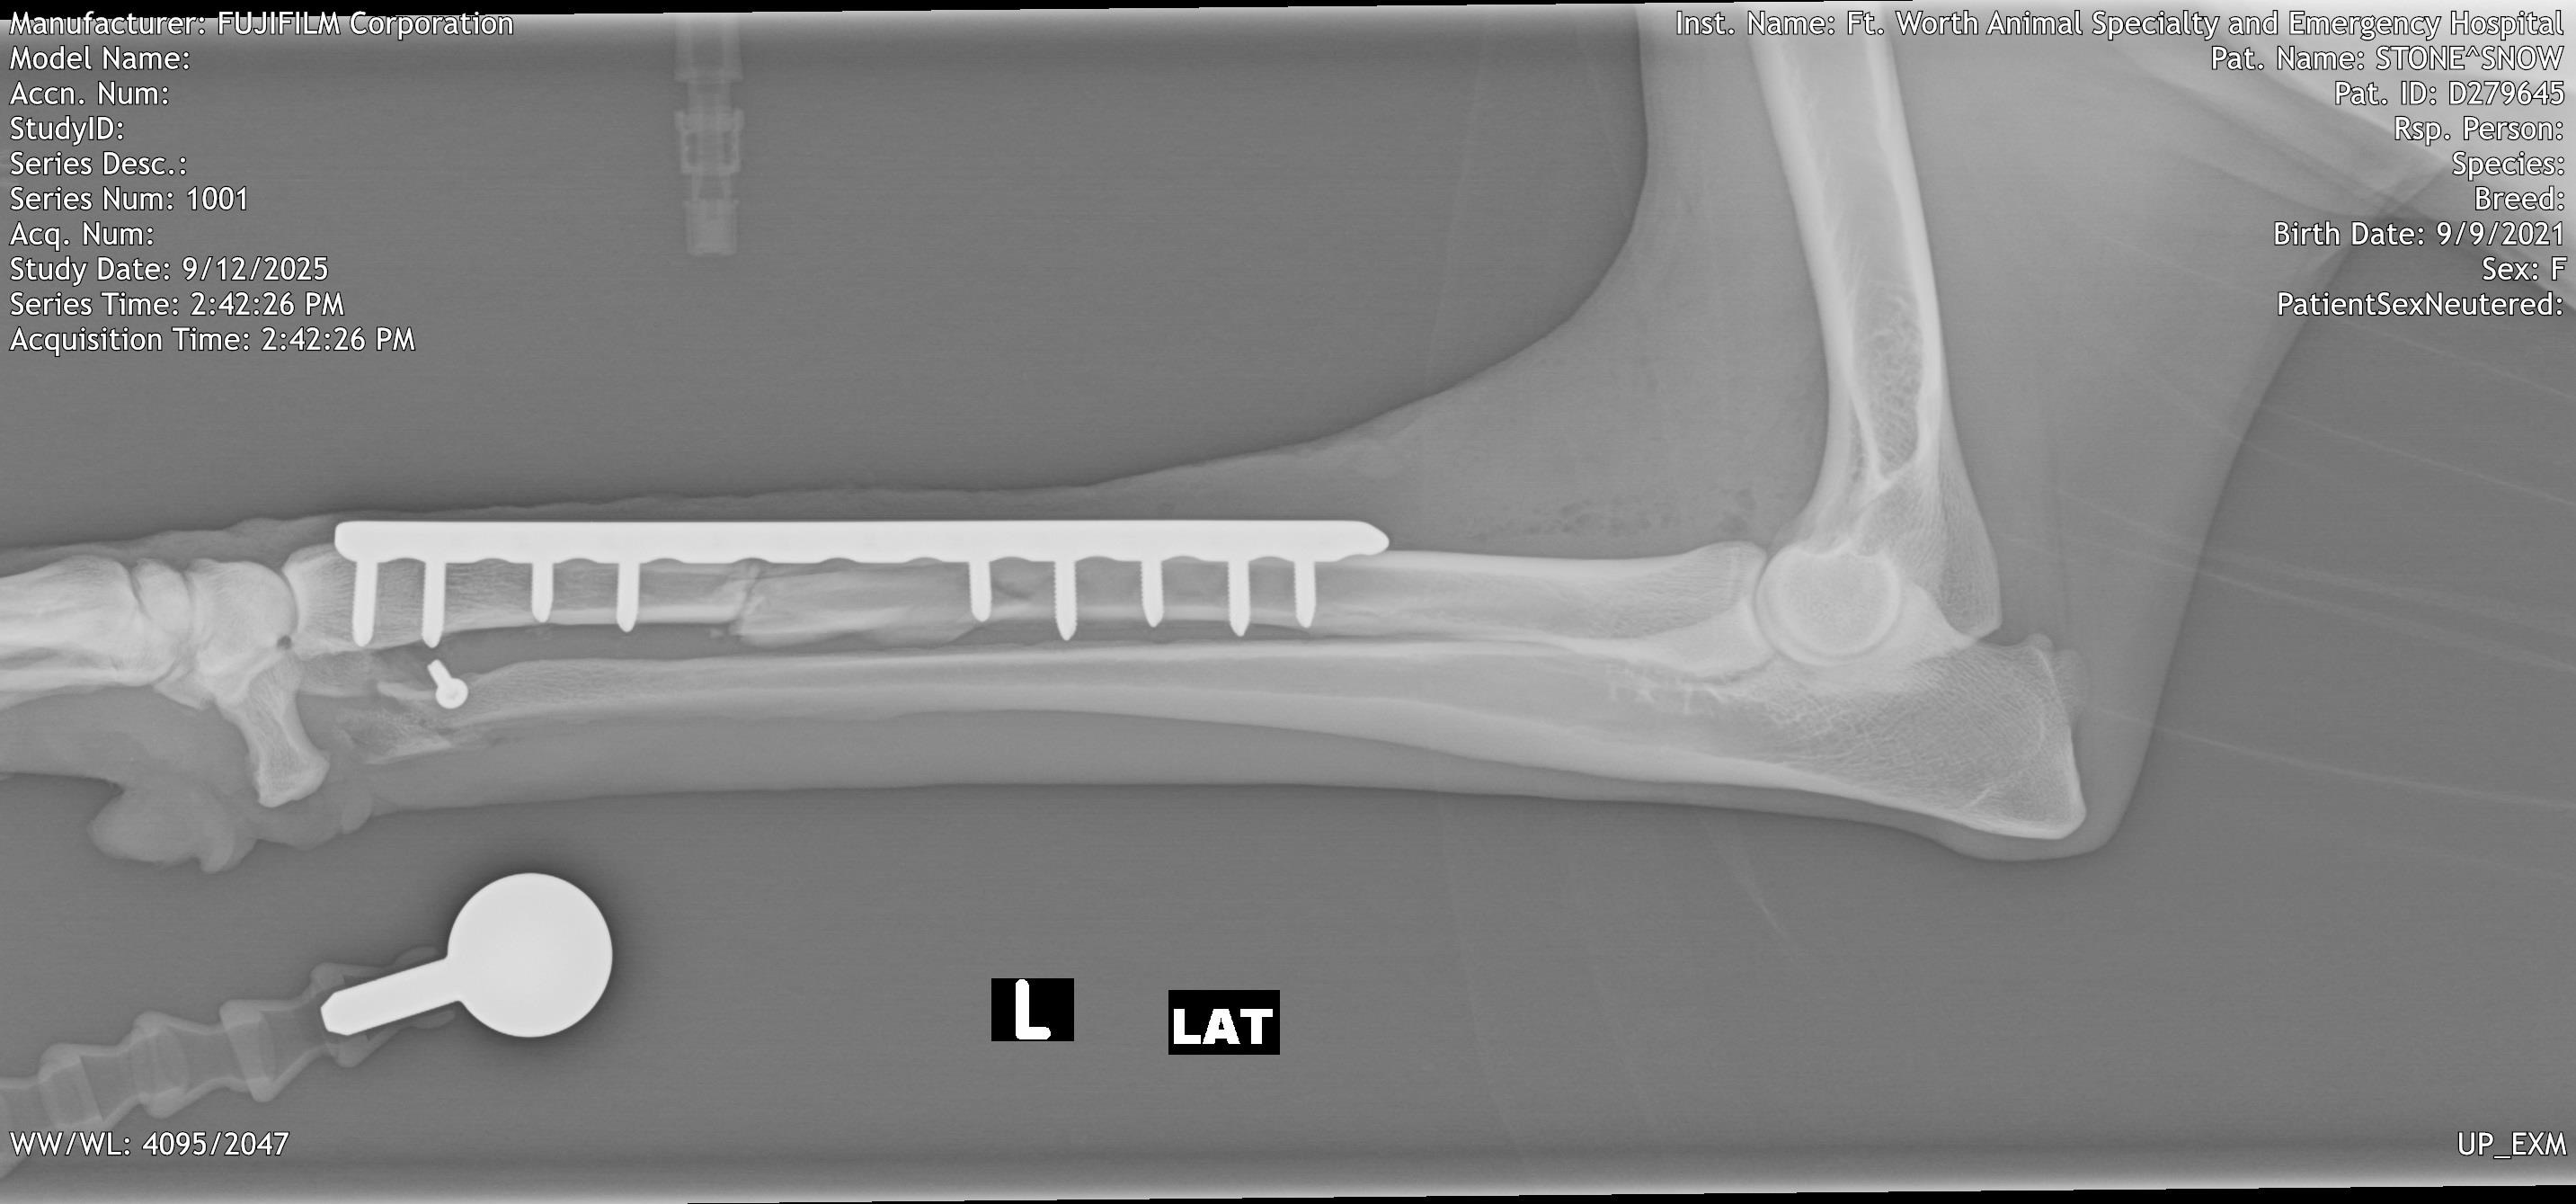

On 9/9/2025, sweet Snow the Borzoi leapt over her backyard fence and was hit by a car. She was rushed to an emergency clinic in Fort Worth, where she was diagnosed with a pneumothorax, multiple lacerations all over her body, and bilateral radial/ulnar fractures. On 9/12/25, she underwent fracture repairs at an orthopedic surgery clinic and had plates put on both legs. She was given a good prognosis.